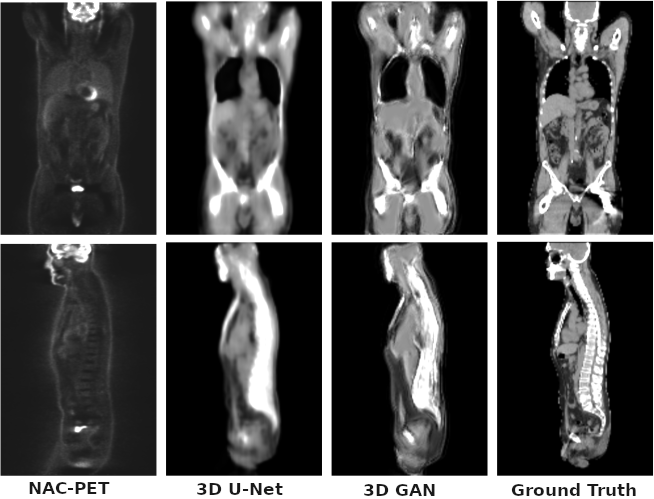

Task: Whole body attenuation map generation using 3D U-Net generative adversarial networks (GANs)

Description: The model is initially trained as a 3D U-Net to learn the mapping from non attenuation corrected 18-F-fluorodeoxyglucose (18F-FDG) PET images to a synthetic Computerized Tomography (sCT) and also to label the input voxel tissue. The sCT image is further refined using an adversarial training scheme to recover higher frequency details and lost structures using context information (3D GAN).

Results: The mean absolute error in the sCT images is 90±20 and 103±18HU with a peak signal to noise ratio of 19.3±1.7 dB and 18.6±1.5, for the base model and the adversarial model respectively. The attenuation correction is tested by means of attenuation sinograms, obtaining a line of response attenuation mean error lower than 1% with a standard deviation lower than 8%. The generated images show good correlation with the unknown structural information.

Remarks: The GAN-synthesized image quality is comparable to the base U-Net method with small attenuation sinograms differences, thus demonstrating its potential for quantitative PET image correction.

The bone tissue is presented using a 3D projection in the following image: